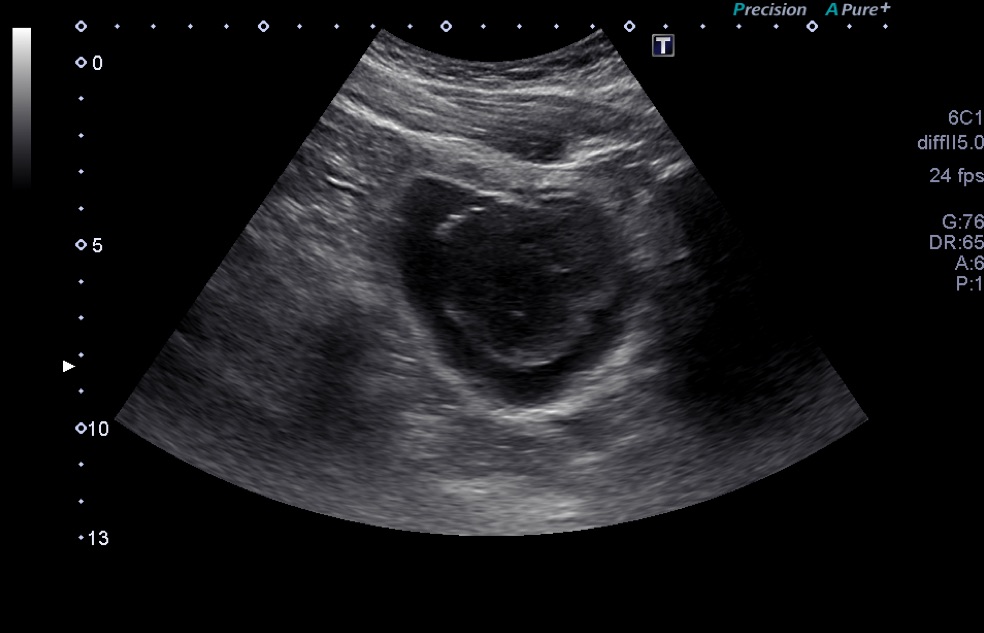

A 2-month-old African American girl presented for a routine well-child visit. Her parents had noticed brown horizontal lines across her abdomen that had been present since birth.